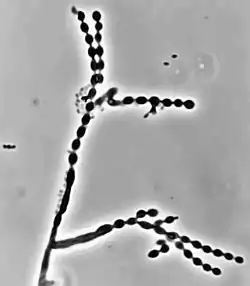

Cladophialophora is a genus of fungi in the family Herpotrichiellaceae. It has 35 species.[1] The genus contains black yeast-like fungi, some of which are species of important medical significance. Cladophialophora bantiana causes the rare brain disease cerebral phaeohyphomycosis.[2] Cladophialophora carrionii is a common cause of chromoblastomycosis in semi-arid climates.[3] Some of the species are endophytes–associating with plants. For example, Cladophialophora yegresii is a cactus endophyte, which is sometimes introduced into humans via cactus spines.[4]